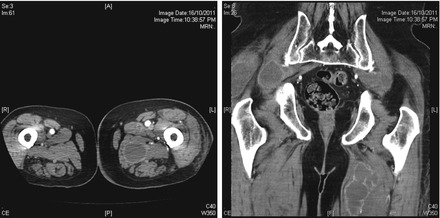

Figure 11.3

CT scan with contrast of the thighs showing bilateral collections within the adductor muscles; transverse section (left), coronal view (right)

The largest collection was located in the left adductor magnus, measuring 3 × 3 × 7 cm in antero-posterior, transverse and craniocaudal diameter. The small collection lied superiorly in the adductor brevis muscle, measuring 2.5 cm. There were poorly circumscribed, low-density changes in the right adductor brevis muscles, measuring 1.8 cm in the axial plane. This suggested the formation of an early collection at an adjacent site.